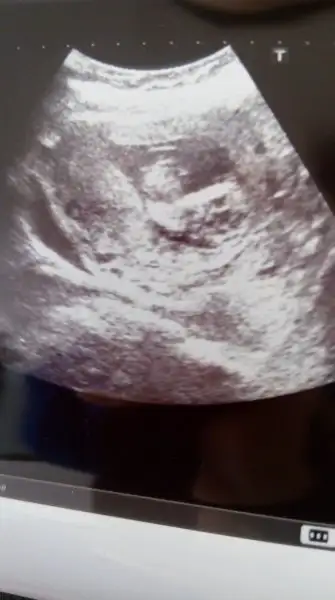

Kızlar ben dayanamadım bebeğimin durumunu merak ettim kontrole gittim sabah.Kanama alanı 3 cm iken 4 cm olmuş :KK43: bu durumdaki hastalara yatış öneririz ama sen evde yatmayı tercih ediyorsun dedi.Her bişeyi kafama taktiğimi da öğrendiği için artık çok cevaplamak istemiyor Sorularımı.bebeğim durumu çok şükür iyiymiş ama çokkkk korkuyorum.Kanama alanı olup evde yatıyor değil mi burada ? Kızlar dua edin lütfen :KK43: